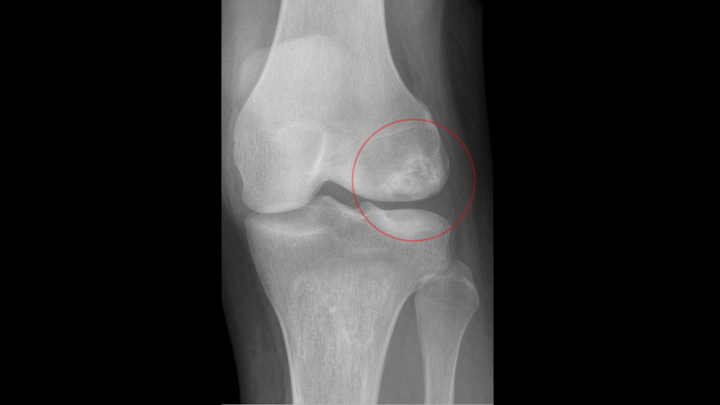

Osteochondritis Dissecans (OCD)